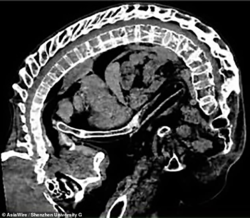

Chińczyk Li Hua, cierpiał przez 28 lat na zesztywniające zapalenie stawów kręgosłupa, które powodowało u niego ekstremalnie ostre zgięcie kręgosłupa, te schorzenie spowodowało że dostał przydomek Folded Man. Z braku pieniędzy na leczenie, oraz z racji że operacja była ówcześnie zbyt ryzykowna, Li byl całkowicie zależny od swojej matki, która opiekowała się nim całodobowo. Z czasem zgięcie kręgosłupa powodowało coraz większy ucisk na serce oraz płuca, przez co życie Li było zagrożone

Po 28 latach lekarze zdecydowali się na kilka ryzykownych operacji, mających za zadanie wyprostowania kręgosłupa Folded Mana.